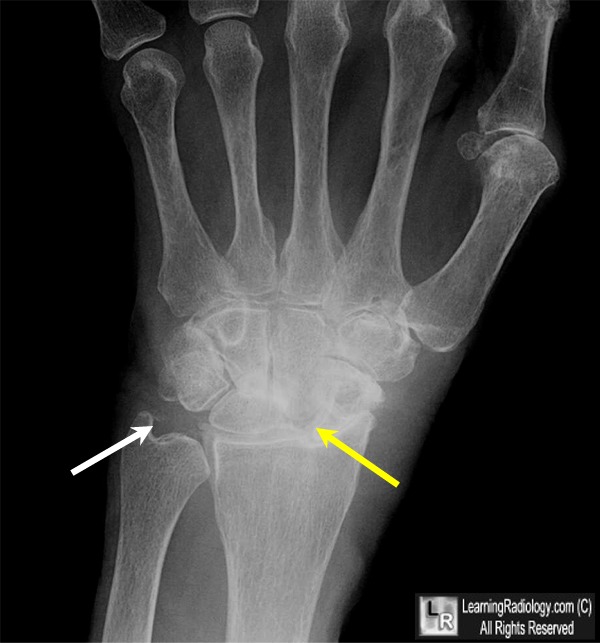

CPPD Calcium phosphate dihydrate deposition disease (CPPD) is a type of arthritis due to crystals being deposited in and around joints. The wrist is ... Fetch Full Source

Calcium Pyrophosphate Dihydrate (CPPD) Deposition Disease

Chondrocalcinosis - Wikipedia, The Free Encyclopedia

Calcium pyrophosphate dihydrate (CPPD) crystal deposition disease, also known as chondrocalcinosis, pseudogout and pyrophosphate arthropathy is a rheumatologic disorder with varied symptoms and signs arising from the accumulation of crystals of calcium pyrophosphate dihydrate in the connective ... Read Article